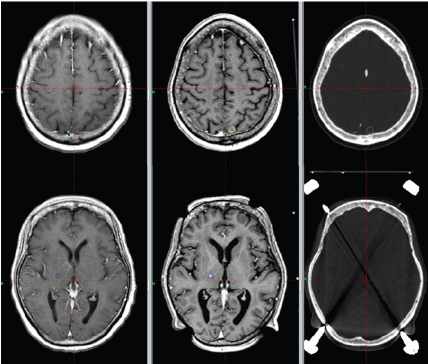

Clinically, high-grade brain tumor boundaries such as those in glioblastoma (GBM) can be highlighted on contrast-enhanced T1-weighted images such as those acquired with T1-weighted magnetization-prepared radio-frequency pulses and rapid gradient-echo (MPRAGE) as well as regular T2-weighted images [23]. Fast fluid-attenuated inversion recovery (FLAIR) images have also been found useful to define tumor edema and possible infiltration [24]. For high grade brain tumors such as GBM T1- weighed high resolution isotropic 3D images acquired postcontrast are being used for tumor contouring and determination of gross target volume (GTV), while a series of T2-weighed and FLAIR images define the clinical target volume (CTV). For brain metastasis and low grade or benign brain tumors there is no tumor invasion to normal brain tissue; therefore, post-contrast high resolution 3D T1-weighted images are sufficient for tumor delineation, especially for SRS treatments (Figure 3).

Figure 3:Brain metastasis. Left: diagnostic T1 spin echo (C + FC) sequence; Center: treatment T1-MPRAGE sequence; Right:. Contours delineate two separate lesions on CT images for planning using MRI images.

Magnetic Resonance Angiography (MRA) is used to define nidus in treatment of arteriovenous malformations (AVMs) [25,26]. Three-dimensional steady state gradient echo sequences such as constructive interference in steady state (CISS) have applications to define the involved trigeminal nerve in SRS trigeminal treatment. CISS signal is heavily T2 weighted, and cerebral spinal fluid around the brain stem shows hypointen sesignal, while normal brain tissue and cranial nerves show no signal. This feature allows contouring of the involved trigeminal nerve root as it emanates from the brainstem [27]. Recently he have shown that using modified high b-value DWI images to define the hypercellular component, and corresponding adjustment to prescribed 95%-isodose volume (PDV) will improves rates of progression-free survival (PFS). Functional MRI (fMRI) is being used regularly for stereotactic brain surgery, and of late many research groups are investigating applications of fMRI during RTP to define and contour OARs [11- 27].